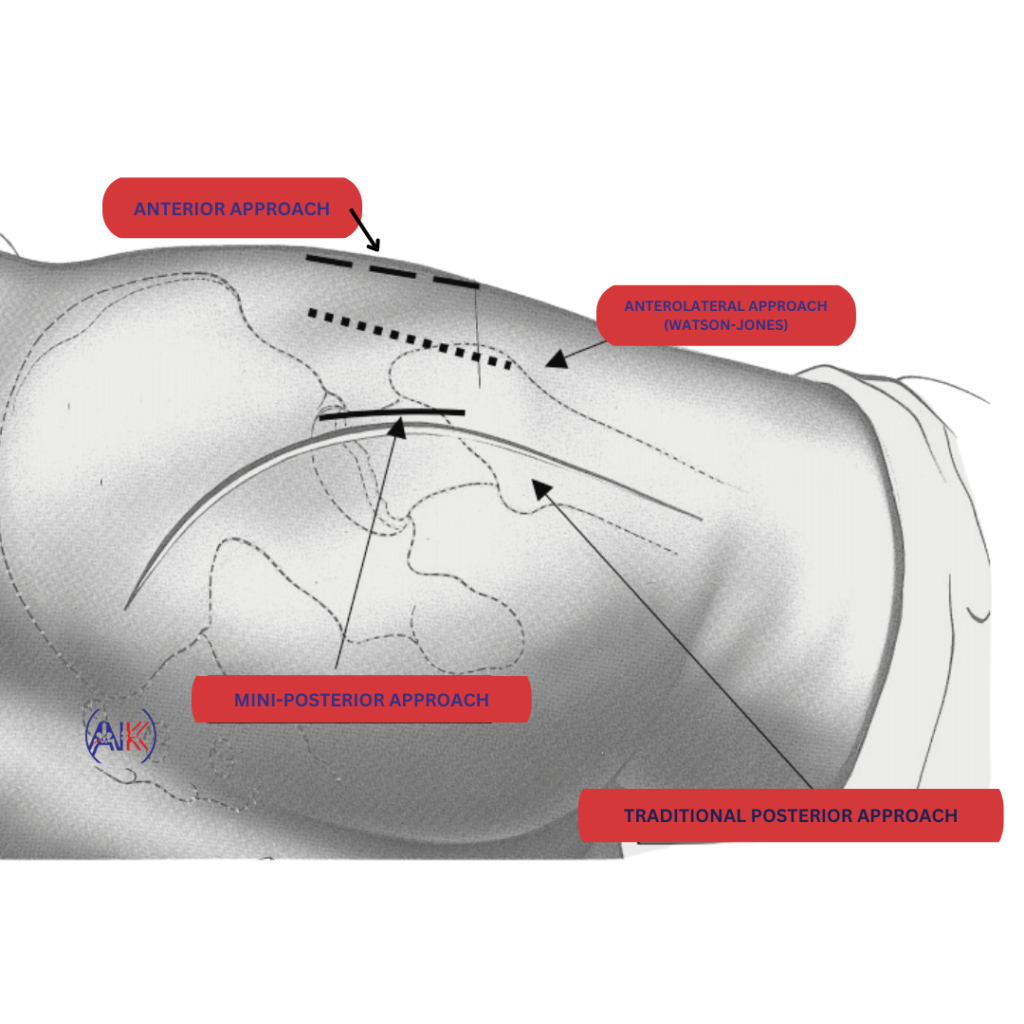

Dr Keeley utilises a range of advanced surgical techniques, selecting the approach that best suits your individual needs and the specific demands of your situation:

Posterior Approach Total Hip Replacement: The posterior approach involves accessing the hip from the back (though the incision is made at the side), offering a broader surgical view via a larger incision. It is particularly advantageous for revision surgeries, where the need for greater access to replace existing implants is paramount, a task sometimes not feasible through the anterior approach.

Minimally Invasive Anterior Approach Total Hip Replacement: Dr Keeley frequently opts for this less invasive technique for initial hip replacements, featuring a smaller incision and reduced tissue damage, which may lead to less pain and quicker recovery. This approach, entering from the front of the hip near the groin, avoids cutting through muscle. For some patients, a “bikini” style incision is possible, enhancing cosmetic outcomes, though this is determined on a case-by-case basis.

Dr Keeley’s adept use of both posterior and anterior approaches is guided by a commitment to providing personalised care, with most studies indicating that while patients undergoing anterior approach hip replacements generally experience quicker recoveries and less pain initially, satisfaction levels between the two approaches even out within a year post-surgery, both delivering excellent long-term results.

Dr Keeley is skilled in both the posterior and anterior hip replacement approaches and the choice of approach used depends on your unique anatomy and specific medical needs.

The posterior approach involves accessing your hip joint from the back, while the anterior approach involves accessing your hip joint from the front, often resulting in less muscle disruption.